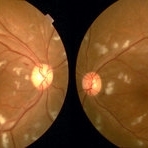

Neurosyphilis

Neurosyphilis

Sep 3 2020 by Ankur S. Gupta, MD, MS

40-year-old male who presented with blurry vision and hand lesions. Hyperreflective nodularity of the retinal pigment epithelium overlying loss of the normal photoreceptor architecture. Disruption of the external limiting membrane. Loss of the photoreceptor inner segment/outer segment band. Punctate hyperfluorescence in the choroid. Transient subretinal fluid.

Photographer: Kenneth Lam; Geisinger Eye Institute

Condition/keywords: neurosyphilis, uveitis